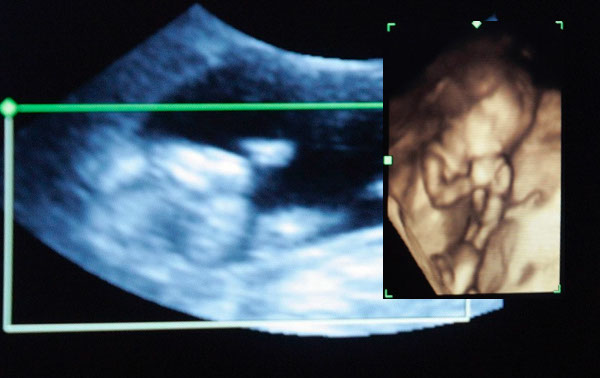

El extraño caso de gemelos semi-idénticos que sobrevivieron cuando eran “típicamente incompatibles con la vida” ultrasonido Una ecografía mostró que Itzamara estaba creando un feto en su abdomen.

Mónica Vega tenía siete meses de embarazo cuando el médico vio algo extraño en su ecografía.

Era su propio bebé, Itzamara, quien estaba creando un f3to en su abdomen.